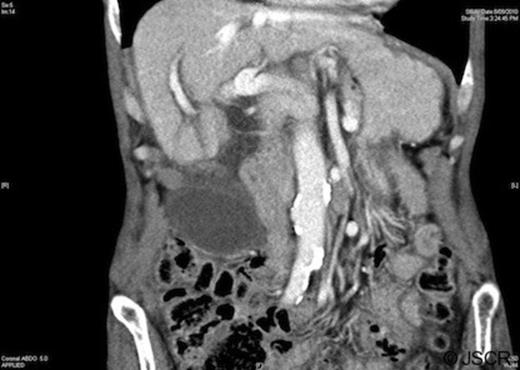

Blood tests were unremarkable, demonstrating a mild anaemia and normal liver function. White cell count (7.8×109/L) and C-reactive protein (<5mg/L) were within the normal range. Abdominal ultrasound and computed tomography revealed a large distended, low-lying gallbladder with a diffusely thickened wall (up to 6mm), pericholecystic fluid and no cholelithiasis (Figure 1). The biliary tree was normal in calibre and ultrasound Murphy’s sign was positive.

Computed tomography demonstrating a low-lying gallbladder with a diffusely thickened wall and pericholecystic fluid